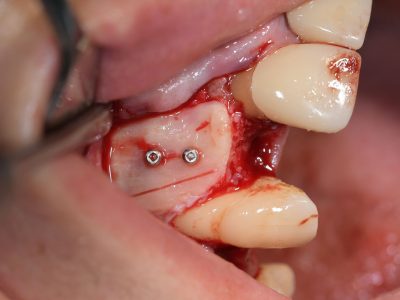

Each case is documented with clinical pictures before, after and during operation. For most of the cases there is surgical video. CBCT before, in the OP day and 4 months after, or longer period of time will demonstrate the volume of buccal bone and soft tissue. Depends of time available, between 13 and 20 clinical cases can be shown.